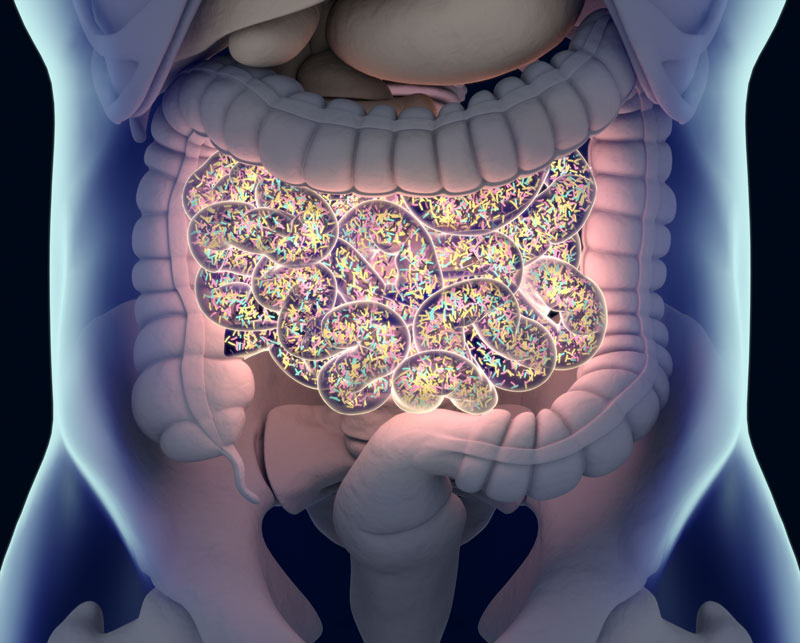

Śmierć zaczyna się w jelitach

Ryba psuje się od głowy, człowiek od jelit.

Wyobraź sobie, że właśnie zjadłeś posiłek bogaty w białka, witaminy i minerały. Aby z tego posiłku pozyskać życiodajne substancje odżywcze, potrzebujesz kilku bilionów dobrych bakterii. Ci probiotyczni pracownicy dosłownie wydobywają cenne składniki odżywcze z masy strawionego jedzenia. Następnie pozyskane przez nie składniki odżywcze transportowane są przez śluzówkę jelita do twojego krwioobiegu, który to z kolei transportuje je do 40 bilionów fabryk w postaci komórek na terenie całego twojego organizmu.

To właśnie dzięki tym substancjom twoje serce bije miarowo, twoja wątroba skutecznie usuwa toksyny, twój mózg sprawnie przetwarza informacje, twoja skóra jest gładka i zdrowa, a twoje włosy lśniące.

Ale jeśli w twoich jelitach jest niewiele dobrych bakterii, cała masa cennych składników odżywczych, które właśnie zjadłeś, wyląduje zwyczajnie w muszli klozetowej, a 40 000 000 000 000 komórek na terenie twojego organizmu zostanie skazanych na zagłodzenie, a ty niestety razem z nimi. Zjawisko to nazywa się głodem komórkowym i w krótkim czasie może doprowadzić do skrajnego wyniszczenia i śmierci twojego organizmu.

Czyli nasza odporność znajduje się w jelitach. IIe jest w tym prawdy?

Jeśli w twoich jelitach nie ma wystarczającej ilości dobrych bakterii, niestrawione jedzenie zaczyna gnić i zalegać w jelitach. Codziennie dochodzi nowa porcja gnijącego niestrawionego jedzenia. Pozbawione wody resztki zamieniają się w twardą masę, powodującą zaparcia.

Dodatkowo produkowane są gazy, a ty kończysz ze wzdętym obolałym brzuchem.

Nie wiem czy słyszałaś o zjawisku zwanym samozatruciem organizmu. Ma ono miejsce, gdy twój organizm dosłownie sam się zatruwa. Dzieje się tak w przypadku przewlekłych zaparć, kiedy kał zawierający toksyny i szkodliwe bakterie nie może wydostać się z jelita grubego i zaczyna tam po prostu gnić. Naczynia kapilarne zaczynają wychwytywać znajdujące się w nim toksyny. Toksyny, które miały być wydalone z twojego organizmu ponownie dostają się do krwioobiegu, który transportuje je do wszystkich części twojego organizmu.

Nieświeży oddech, nieprzyjemny zapach ciała, śmierdzące stopy wydają się być najmniej niebezpiecznymi objawami. Samozatrucie w wyniku przewlekłych zaparć prowadzi do dewastacji jelit, czego skutkiem są hemoroidy, polipy, wrzody, zespół jelita drażliwego, choroba Leśniewskiego-Crohna i wreszcie rak. Inne objawy samozatrucia obejmują bóle głowy, zamglenie umysłu, zmęczenie, nadmierny przyrost masy ciała, problemy trawienne, słaby apetyt, alergie, obrzęk nóg czy szarą cerę.

Dr Kellog mówi, że „Śmierć zaczyna się w jelicie grubym” i jest to rzeczywiście prawda.